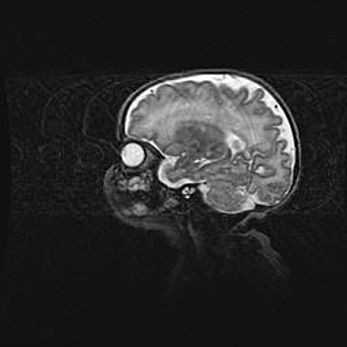

Сообщающаяся гидроцефалия. Кистозная энцефаломаляция головного мозга.

Возраст: 3 месяца 4 дня

Вес: 3100 г

Пол: женский

Окружность головы: 34 см

Срок гестации: 31 неделя

Кистозная энцефаломаляция головного мозга - одна из форм поражения головного мозга в детском возрасте. Характеризуется возникновением множественных и распространённых кист в коре, белом веществе и подкорковых образованиях головного мозга у плодов, новорождённых и детей раннего возраста. Развитие кистозной энцефаломаляции связано с внутриутробной асфиксией и гипотонией, родовой травмой, тромбозом синусов, пороками развития сосудов, инфекциями, сепсисом и другими причинами. Наиболее значимые инфекционные агенты: вирусы простого герпеса, цитомегалии, краснухи, токсоплазмы, энтеробактерии, золотистый стафилококк и другие.